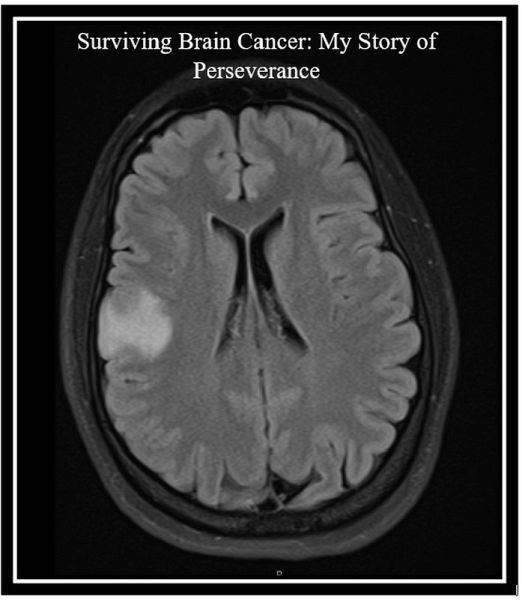

And I was right. That relentless intuition led me to the truth: brain cancer.